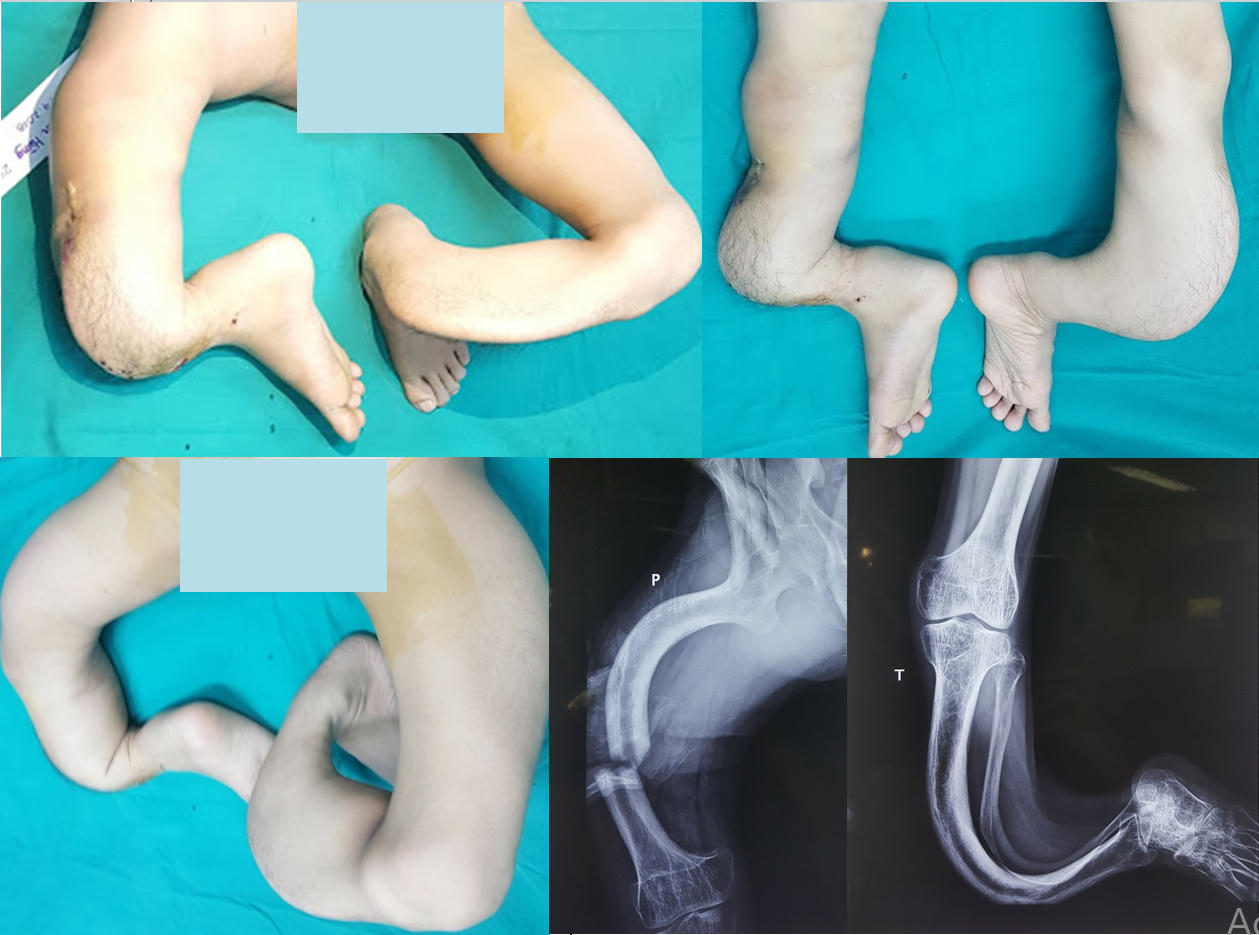

Các bác sĩ chuyên ngành của Bệnh viện Trung ương quân đội 108 kinh ngạc trước đôi chân dị dạng của nam bệnh nhân. "Hơn 30 năm làm nghề, tôi chưa bao giờ nhìn thấy một dị dạng phức tạp đến kỳ lạ như thế", Đại tá, GS.TSKH.TTND Nguyễn Thế Hoàng, Phó Giám đốc Bệnh viện TWQĐ108 chia sẻ. "Hình ảnh X-quang cả hai chi dưới cho thấy toàn bộ hệ thống xương khớp ở vùng đùi, cẳng chân và bàn chân đều bị biến dạng cong vẹo và phức tạp theo nhiều chiều, nhiều hướng khác nhau. Chiều dài xương hai bên là hoàn toàn khác biệt. Các cấu trúc phần mềm quan trọng để che phủ, nuôi dưỡng và bảo đảm hoạt động chức năng cho cả hai chân như: da, cân, cơ, gân, mạch máu và thần kinh cũng bị thay đổi hoàn toàn và tạo nên tình trạng chỗ căng chỗ chùng. Do không đi lại tỳ nén nên xương bị thưa loãng nặng".

Sau 8 tháng điều trị và trải qua 3 lần phẫu thuật, hiện giờ hai chân của bệnh nhân đã hoàn toàn bằng nhau. Vận động cảm giác của 2 bên chi thể được phẫu thuật đều rất tốt. Do có cảm giác tốt và đạt được sự cân bằng về chức năng vận động của các khối cơ gấp - duỗi và xoay trong xoay - ngoài cả hai chân nên bệnh nhân sẽ hoàn toàn có thể đi lại được như người bình thường. Hiện tại, do can xương còn chưa vững nên bệnh nhân cần được tập thêm hồi phục chức năng và cố định nẹp bột bổ sung.

"Sự vất vả và quyết tâm của chúng tôi đã được đền đáp xứng đáng bằng niềm vui và tương lai tươi sáng của bệnh nhân",GS.TSKH.TTND Nguyễn Thế Hoàng bày tỏ. "Chúng tôi có đầy đủ cơ sở để tin rằng, chỉ sau 4-6 tháng nữa thôi, bệnh nhân không những chỉ đi lại mà còn hoàn toàn có thể chạy nhảy trên chính đôi chân của mình giống như những bạn bè bình thường cùng trang lứa với cậu".